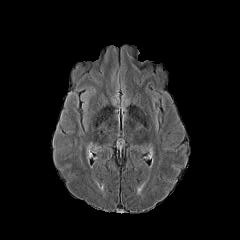

We observe that the generated normal-looking from ANT-GAN can also be used to directly segment the image, since the only difference between a synthesized normal-looking image and its real abnormal counterpart is region with the lesion. To illustrate this, we calculate the absolute difference between x𝑥x and 𝒢A2N(x)subscript𝒢A2N𝑥\mathcal{G}_{\rm{A2N}}(x) and show the segmentation after binary thresholding at 0.1 in Figure 9.

(a) Tumor x𝑥x

(b) 𝒢A2N(x)subscript𝒢A2N𝑥\mathcal{G}_{\rm{A2N}}(x)

(c) Prediction

(d) Label

Figure 9: Example segmentation obtained by taking the absolute difference between the real tumor MRI x𝑥x and the generated normal-looking MRI 𝒢A2N(x)subscript𝒢A2N𝑥\mathcal{G}_{\rm{A2N}}(x), after binarization at a preset threshold.